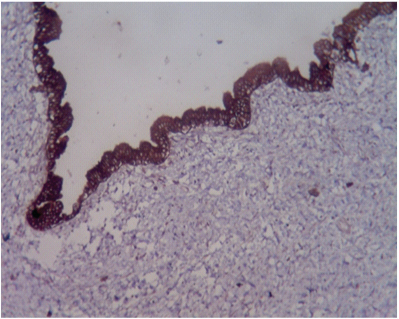

Gross examination showed an unilocular cystic lesion measuring 17 x 10 cm with a pale grey smooth cyst wall. [Table/Fig-2] of thickness that varied from 0.2 cm to 0.8 cm. On histology of the lesion showed a cyst wall internally lined by an epithelium of biliary type of columnar epithelium with focal pseudostratification and basally oriented nuclei with foci of apical mucin, no nuclear or cellular atypia and an underlying mesenchymal stroma that was resemblent of the ovarian stroma. Hence a diagnosis of biliary cystadenoma was offered [Table/Fig-3a,b] Immunohistochemistry of the tumour was positive for Cytokeratin in the epithelial cells [Table/Fig-4]. A final diagnosis of biliary cystadenoma was made.

Photomicrograph showing cytokeratin positivity in epithelial cells.

Pancytokeratin (100X).